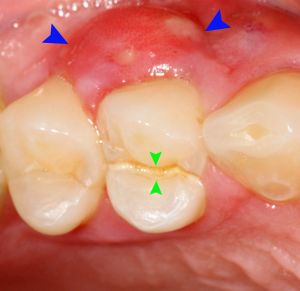

Tályog a szájban – képek

A tályog a szájban képek forrása a Wikipédia.